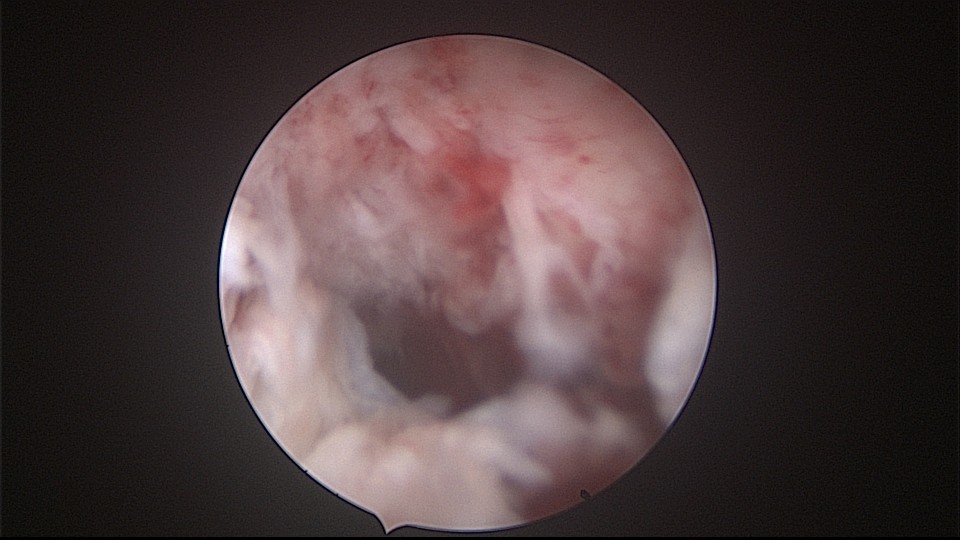

患者52岁,G2P1,顺产1次。安环27年,外院取环失败。病人肥胖,B超提示子宫前位,节育环距宫底0.9cm。子宫极度前倾前屈位,宫腔镜见宫颈管组织杂乱,宫颈管上段右前壁见假道,膨宫不良,视野模糊,寻找宫腔方向困难,准备B超监护过程中,拆走扩阴器,腹部下压子宫,终于寻找到了宫颈内口,看到了爱母环下端,异物钳牵拉出节育环,再次探查宫腔,无其他异常。